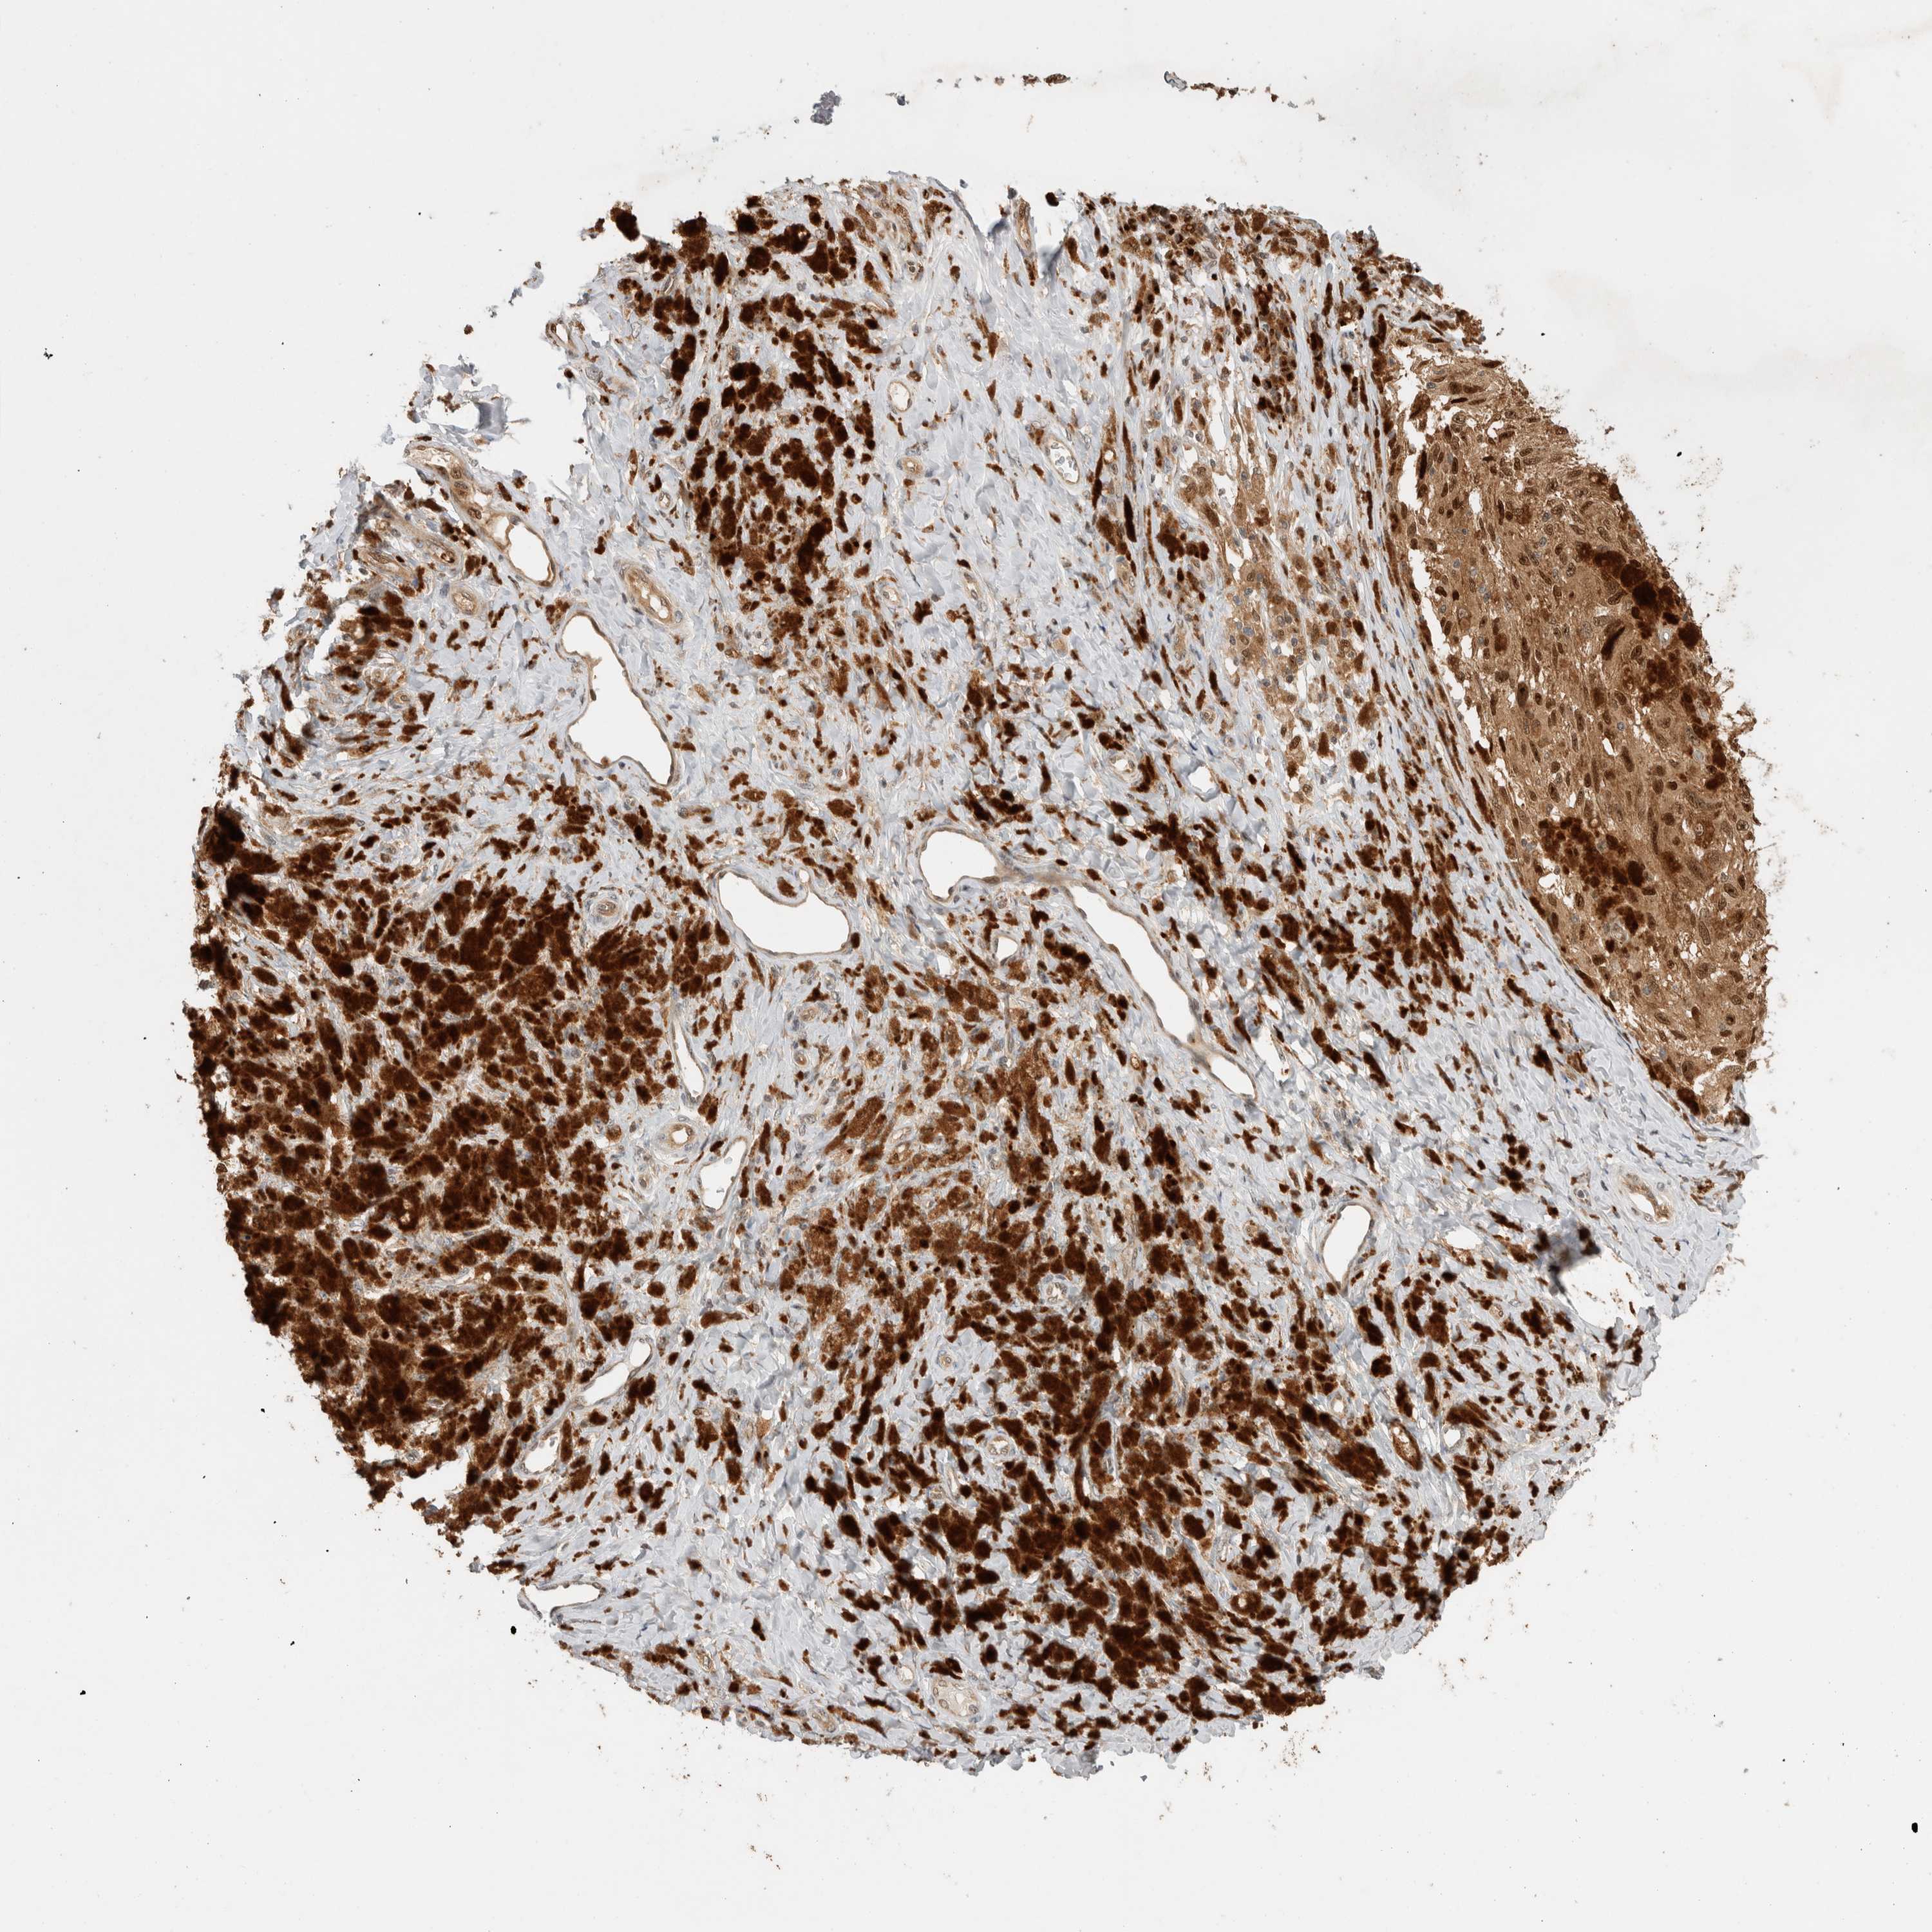

MELANOMA - Protein expressioni

A mouse-over function shows sample information and annotation data. Click on an image to view it in a full screen mode. Samples can be filtered based on level of antibody staining by selecting one or several of the following categories: high, medium, low and not detected. The assay and annotation is described here.

Note that samples used for immunohistochemistry by the Human Protein Atlas do not correspond to samples in the TCGA dataset.

Antibody stainingi

Antibody staining in the annotated cell types in the current human tissue is reported as not detected, low, medium, or high, based on conventional immunohistochemistry profiling in selected tissues. This score is based on the combination of the staining intensity and fraction of stained cells.

Each image is clickable and will lead to virtual microscopy that enables deeper exploration of all samples and also displays staining intensity scores, fraction scores and subcellular localization as well as patient and tissue information for each sample.

Antibody HPA024046

Antibody HPA024503

Antibody HPA024772

Staining

High

Medium

Low

Not detected

Intensity

Strong

Moderate

Weak

Negative

Quantity

>75%

75%-25%

<25%

None

Location

Nuclear

Cytoplasmic/membranous

Cytoplasmic/membranous,nuclear

Malignant melanoma, NOS

Malignant melanoma, Metastatic site